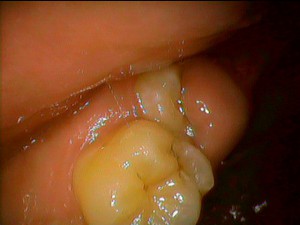

今日は親知らずのあたりから歯肉の痛み、歯の痛みがあるということで患者様が来院されました。 レントゲンや歯肉の検査、歯の状態などを検査させていただきました。痛みを訴えているところの歯がまだ完全に生えてきていないので、歯肉がかぶさっており、炎症を起こしている状態でした。

幸いなことに、まだ虫歯ではなかったので歯と歯肉の間の歯肉ポケットの洗浄と歯茎ケアをおこないました。全体的にお口の中の細菌数が下がり、歯肉ポケット内に抗生物質のお薬をいれて次回再び落ち着いていれば大丈夫だと思われます。